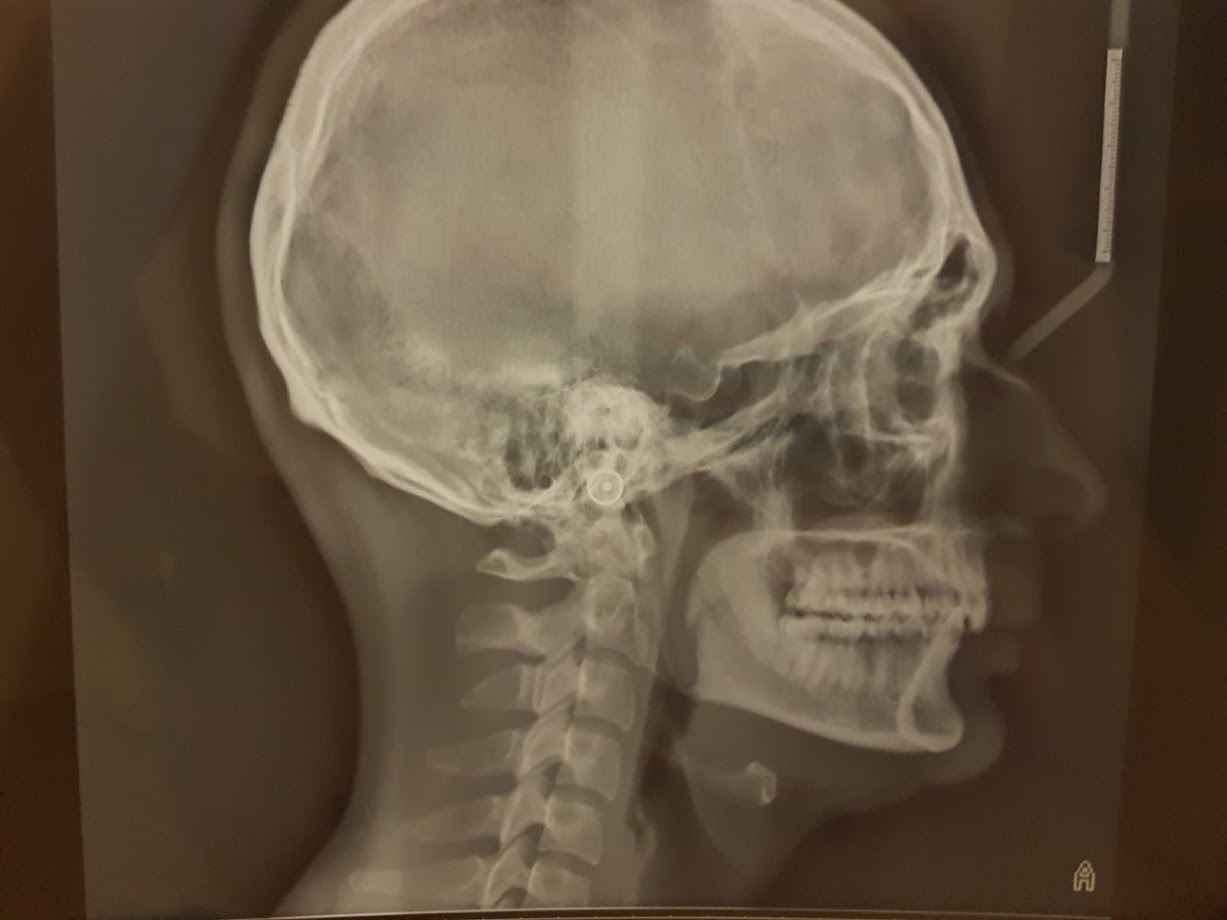

Caro Signor Alessandro, buongiorno. "improvvisamente da un anno soffro di disturbi cranio mandibolari molto fastidiosi". Improvvisamente? Questo mi la scia molto perplesso! Sono totalmente e pienamente d'accordo col Dottor Passaretti! Non è postando on line foto e radiografie che può avere una Diagnosi! Deve essere visitato da un bravo Gnatologo, per prima cosa. Poi si valuterebbe per gli altri eventuali Specialisti. Dice di avere rumori articolari. Il problema è che di rumori ce ne sono diversi con significati diversi! C'è il Click che è un rumore veloce, di ottava musicale alta, peculiare di un dislocamento menisco condilare, rumore presente in apertura e/o in chiusura e che scompare con la protrusiva!

Lo scroscio di sfregamento che invece di essere istantaneo e veloce, è lento e si ha in tutta l'ampiezza del movimento di apertura e/o chiusura delle arcate ed è di ottava musicale bassa e non alta!

Io mi occupo di questo da moltissimi anni. Occorre però una seria e corretta valutazione Clinica Semeiologica con anche sondaggio parodontale oltre che valutazione delle tre curve di compensazione, di Spee e di Wilson per il piano occlusale rispettivamente sagittale e frontale. La terza curva di Compensazione da valutare e quella di Monson che non è altro che una sfera immaginaria che serve per allineare le cuspidi dei denti posteriori con i margini incisali degli incisivi frontali e del movimento condilare di Bennet oltre che le tre disclusioni citate e in Relazione Centrica ed Over-Jet (sovraggetto ossia di quanto i denti superiori sopravanzino gli inferiori) e L'Over Bite (di quanto i superiori coprano gli inferiori) e il Movimento di Bennet a livello della Testa del Condilo!!! Legga nel mio profilo "Visita Parodontale", Le sarà molto utile! Come vede i "problemi sono più complessi di quanto possa immaginare, pur essendo di normalissima Routine Odontoiatrica ma Colta e di Qualità! La Terapia dipende da tutte queste valutazioni e da tanto altro!

Le spiego ancora qualche cosa:A volte bisogna ricorrere all'uso di un arco facciale di trasferimento, essenziale per rilevare i rapporti spaziali delle sue arcate con la base cranica e per il montaggio dei suoi modelli di studio su un articolatore a valore medio per studiare la gnatologia della sua bocca e la sua clinica e le sue articolazioni con angoli di spostamenti come l'angolo o movimento di Bennet tra il piano sagittale ed il movimento del condilo in lateralità della mandibola che è la fotografia reale della sua patologia! Per esempio, maggiore è il movimento di Bennet e minore è l'altezza delle cuspidi e viceversa, quindi l'occlusione e il rapporto delle cuspidi tra antagonisti e tra di loro, incidono sul movimento di bennet e sulla misurazione dell'angolo che forma con le strutture citate ed in ultima analisi con le patologie del lato lavorante e di quello non lavorante della testa dei condili. Questo movimento di bennet può essere immediato o progressivo a seconda delle patologie presenti o non patologie presenti, ovviamente!Il movimento di lateralità è bene studiarlo anche clinicamente con la palpazione perché è determinato dalla contrazione dello pterigoideo esterno del lato opposto a quello verso cui si sposta la mandibola. Un dolore durante questa palpazione indica una contrattura del muscolo e quindi la presenza di una patologia articolare. Palpazione che va fatta non solo in lateralità ma anche in apertura sui "trigger-point" per valutare la presenza di contratture muscolari in sede dello Pterigoideo e del Massetere in particolare!